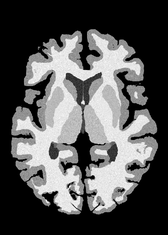

4.2 Registration to a 100 micron ex-vivo brain MRI volume

To showcase the efficacy of our method on real large scale images, we register a 250 in-vivo MRI image (Lüsebrink et al., 2017) to a 100 ex-vivo FLASH human brain volume (Edlow et al., 2019). This represents an inverse problem with more than 11.2B optimizable parameters (compared to 20M for clinical datasets), or 44.8GB of GPU memory. The entire problem does not fit on most GPUs, necessitating distributed multimodal registration. We optimize a composite transform - affine followed by a diffeomorphic mapping; details can be found in Section E.1. Multimodal deformable registration took 58 seconds on 8 NVIDIA A6000 GPUs, which is unprecedented at this resolution. Fig. 6 shows qualitative results, highlighting the ability to register highly detailed structures such as cerebellar white matter; these structures are not visible at macroscopic scales. The resultant advantages of performing registration at this scale can allow researchers to characterize the neuroanatomy at microscopic resolutions and allow morphometric analysis of cortical layers and subcortical nuclei among other structures.